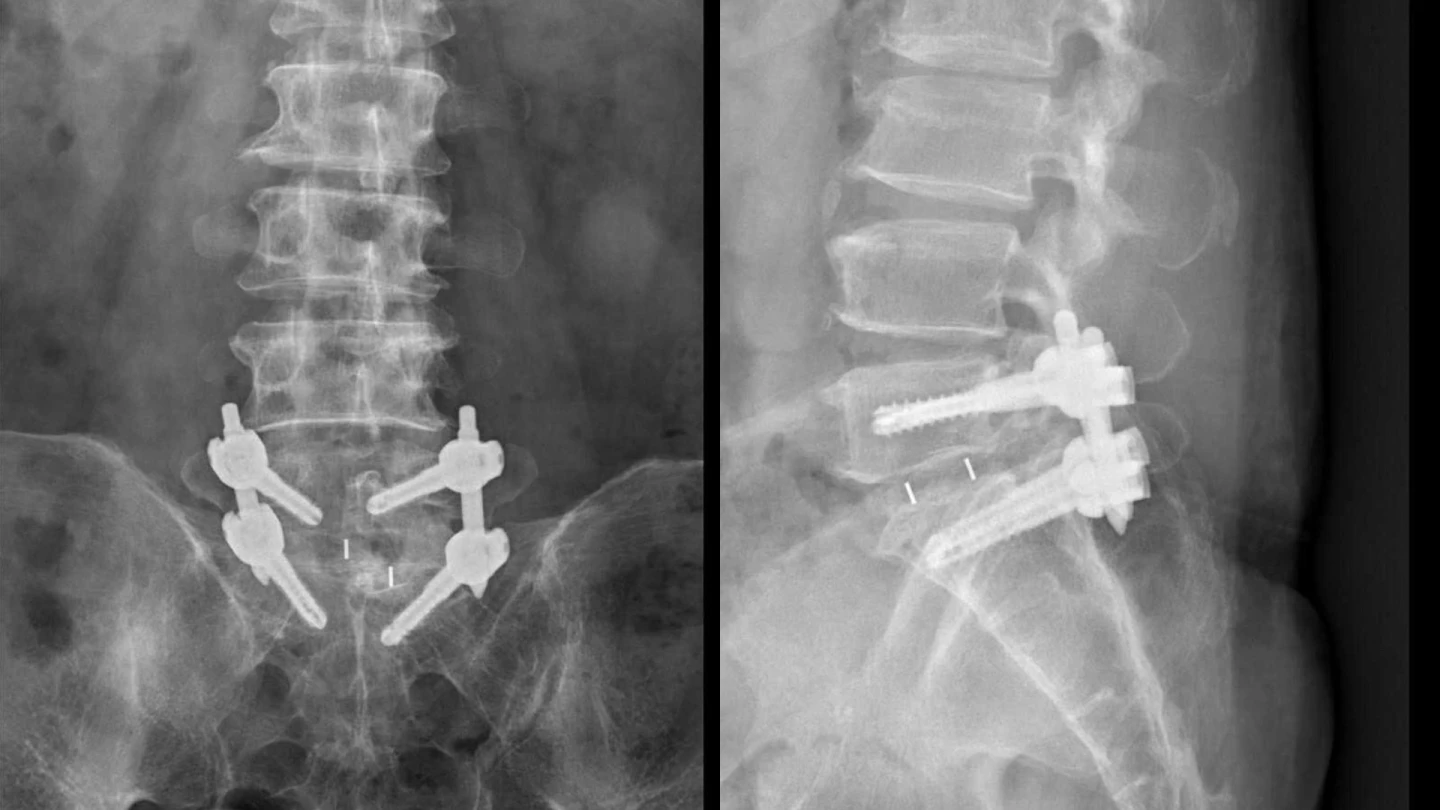

影像檢查顯示,張先生的第五節腰椎椎弓骨折合併脊椎解離,花蓮慈院神經脊椎微創外科主任洪祥益指出,這類病人多半表現為腰痠背痛、久坐久站困難,通常可先藥物治療觀察,但張先生疼痛異常明顯,手術中發現脊椎關節內長滿痛風石,如白色黏稠物般附著在神經與關節縫隙間,不清乾淨會持續引發神經發炎與疼痛,甚至比坐骨神經痛更強烈。

張先生接受脊椎微創手術治療,醫療團隊透過顯微鏡,在不傷及神經的情況下,仔細將痛風石刮除清理,再以微創固定融合手術完成治療。